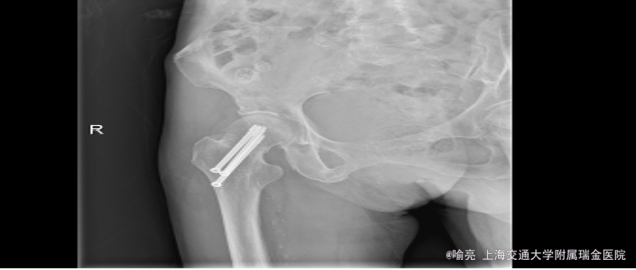

诊断:右侧股骨颈骨折 治疗:右侧股骨颈骨折闭合复位内固定术

随访:患者诉术后疼痛明显缓解。 讨论:对于老年且一般情况很差的患者,给予内固定治疗能极大得改善预后。对于气管插管可能有脱管困难的患者,能否在局麻下行内固定治疗?